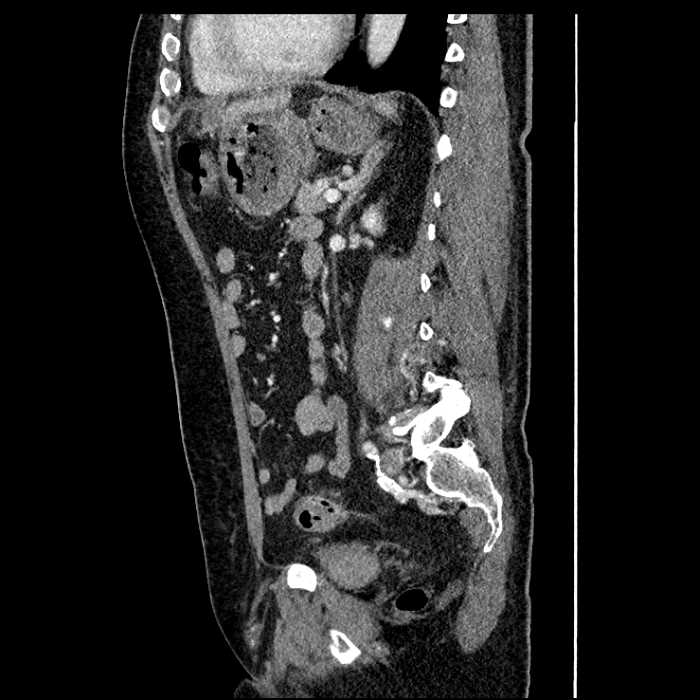

• Large fluid density structure in hepatic segments 7 and 8 measuring 10 x 7 x 7 cm with internal septation and circumferential ill-defined low density compatible with edema

• Peripherally enhancing subcapsular collections along the anterior margin of the left hepatic lobe measuring 3 x 1 cm and 2 x 1 cm

• Mild mural thickening of a segment of the sigmoid colon with adjacent fat stranding and a 1.5 cm fluid and gas collection along the tip of an inflamed diverticulum

• Loss of the normal fat plane between this collection and adjacent loops of small bowel, which demonstrate mural thickening

Acute sigmoid diverticulitis complicated by a small contained perforation and a large abscess in the right hepatic lobe. Additional small subcapsular abscesses along the anterior margin of the left hepatic lobe.

Additionally, loss of the normal fat plane between the peridiverticular collection and adjacent thickened loops of small bowel raises the potential for an enterocolonic fistula.

• The classic CT imaging appearance is a double target sign with internal low density surrounded by an internal enhancing rim (capsule) and a low density external rim (edema)

Hepatic abscess showing the double target sign with low density internally surrounded by a thin inner enhancing rim (red arrow) and ill-defined outer low density rim (yellow arrow). Blue arrow indicates an internal septation. Red arrows: additional smaller subcapsular abscesses. Red arrow: focal contained perforation associated with diverticulitis.